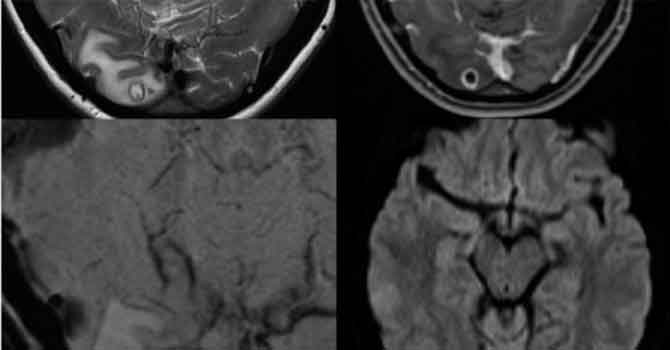

Doktorlar baş ağrısından şikayet eden kadının beyninde tenya larvası buldu